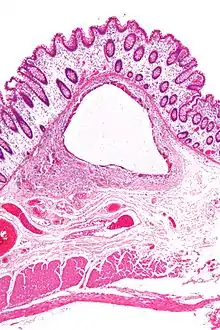

A lung cyst, or pulmonary cyst, encloses a small volume of air, and has a wall thickness of up to 4 mm.[3] A minimum wall thickness of 1 mm has been suggested,[3] but thin-walled pockets may be included in the definition as well.[4] Pulmonary cysts are not associated with either smoking or emphysema.[5]

A lung cavity has a wall thickness of more than 4 mm.[3]

- Pneumatosis intestinalis, air or gas cysts in the bowel wall

- Gastric pneumatosis (or gastric emphysema) is air or gas cysts in the stomach wall[6]